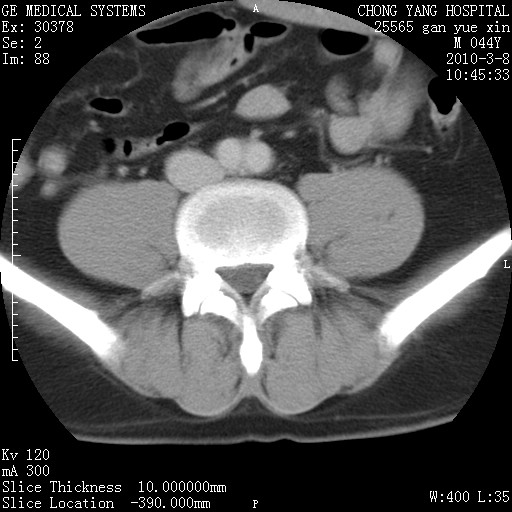

标题: CT24940:主动脉增强,典型病例。 [打印本页]

标题: CT24940:主动脉增强,典型病例。

夹层动脉瘤。

动脉夹层

夹层动脉瘤,典型

主动脉夹层。

动脉夹层的分型:

⒈debakey分型:根据主动脉夹层累及部位,分为三型:ⅰ型:原发破口位于升主动脉或主动脉弓部,夹层累及升主动脉、主动脉弓部、胸主动脉、腹主动脉大部或全部,少数可累及髂动脉。ⅱ型:原发破口位于升主动脉,夹层累及升主动脉,少数可累及部分主动脉弓。ⅲ型:原发破口位于左锁骨下动脉开口远端,根据夹层累及范围又分为ⅲa,ⅲb。ⅲa型:夹层累及胸主动脉。ⅲb型:夹层累及升主动脉、腹主动脉大部或全部。少数可累及髂动脉。

⒉stanford分型:a型:夹层累及升主动脉,无论远端范围如何。b型:夹层累及左锁骨下动脉开口以远的降主动脉。

夹层动脉瘤,少量胸水

夹层动脉瘤;左侧少量胸腔积液。

典型主动脉夹层。